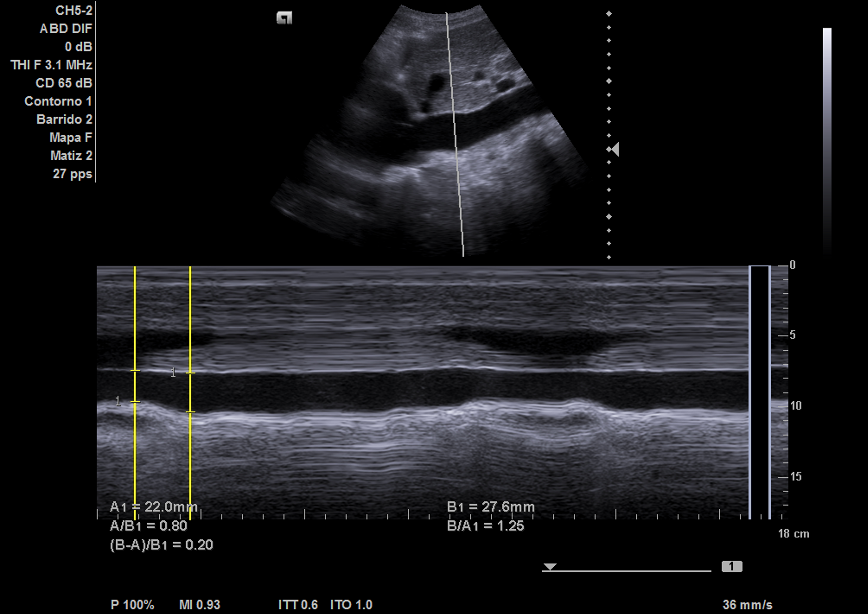

Hallazgos ecográficos

Ecografía pulmonar: derrame pleural bilateral con múltiples líneas B.

Ecocardiografía: importante dilatación auricular izquierda y derecha, vena cava no colapsable.